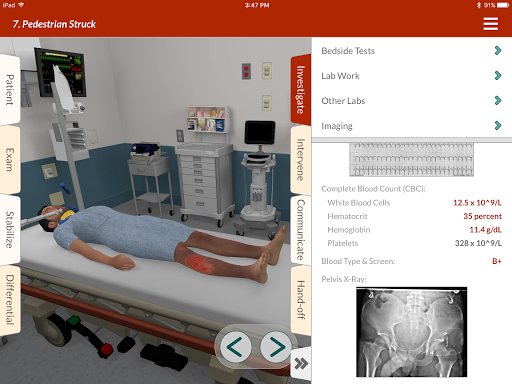

• 200+ thư viện trường hợp được biên soạn và đánh giá bởi các bác sĩ lâm sàng chuyên gia

• Hơn 30 chuyên khoa chẩn đoán, bao gồm Y học cấp cứu, Sản phụ khoa và Nhi khoa

• Hơn 20 hình đại diện thực tế, bao gồm bệnh nhi và người lớn

• Cải tiến trường hợp chấn thương & quần áo đường phố

Chúng tôi đã cập nhật tất cả các trường hợp chấn thương với các hoạt động ổn định phù hợp hơn. Bệnh nhân chấn thương bây giờ bắt đầu trong trang phục đường phố!

- Giá trị phòng thí nghiệm Phạm vi bình thường -

Giá trị phòng thí nghiệm bằng số hiện nay cách phạm vi bình thường cho bệnh nhân của bạn.